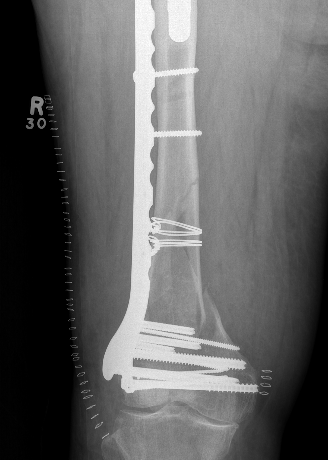

Dual plate

Indications

Significant comminution

Loss of medial cortical buttress

Technique

Results

- 21 comminuted distal femur fractures

- increased union rates with double v single plate

- increased revision rate with single plate